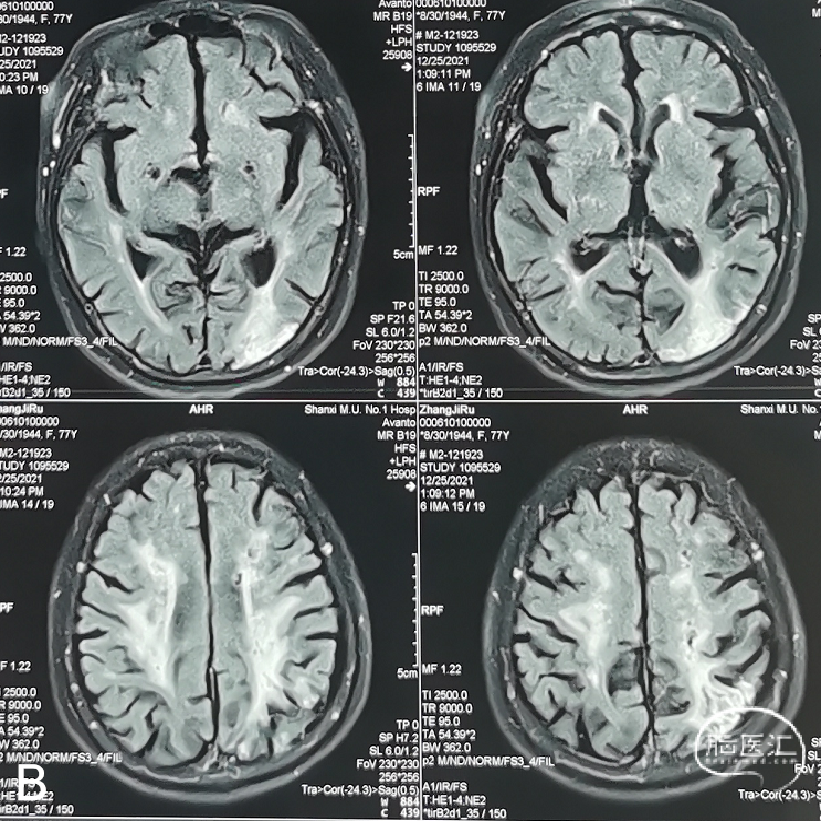

术前影像学检查结果

外院行头颅核磁示:左侧额顶枕叶急性脑梗死;颅内多发陈旧性脑梗死。

外院行脑血管造影示:左侧颈内动脉眼动脉段重度狭窄。

1. 手术指征:患者DSA示左侧颈内动脉眼动脉段重度狭窄;核磁显示左侧分水岭脑梗死